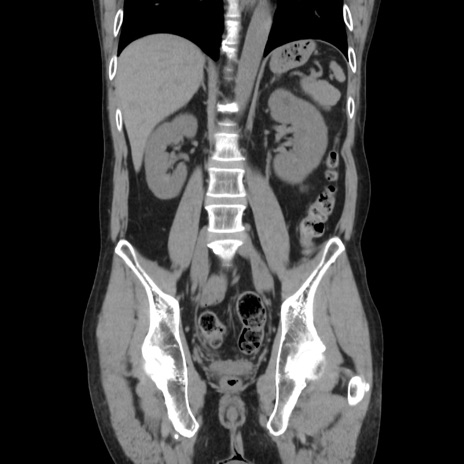

症例37(冠状断像)

【症例】40歳代 男性

【主訴】腹痛

【現病歴】4時間ほど前に電車に乗車中に臍部上より腹痛出現。徐々に増悪し起立困難となり、救急外来受診。生ものは数日食べていない。今朝お雑煮を食べた。

【身体所見】BT 36.8℃、BP 117/84mmHg、HR 91/min、SpO2 97%、苦悶様、腹部:臍上部広範囲圧痛あり、反跳痛±

【データ】WBC 8100、CRP 0.03